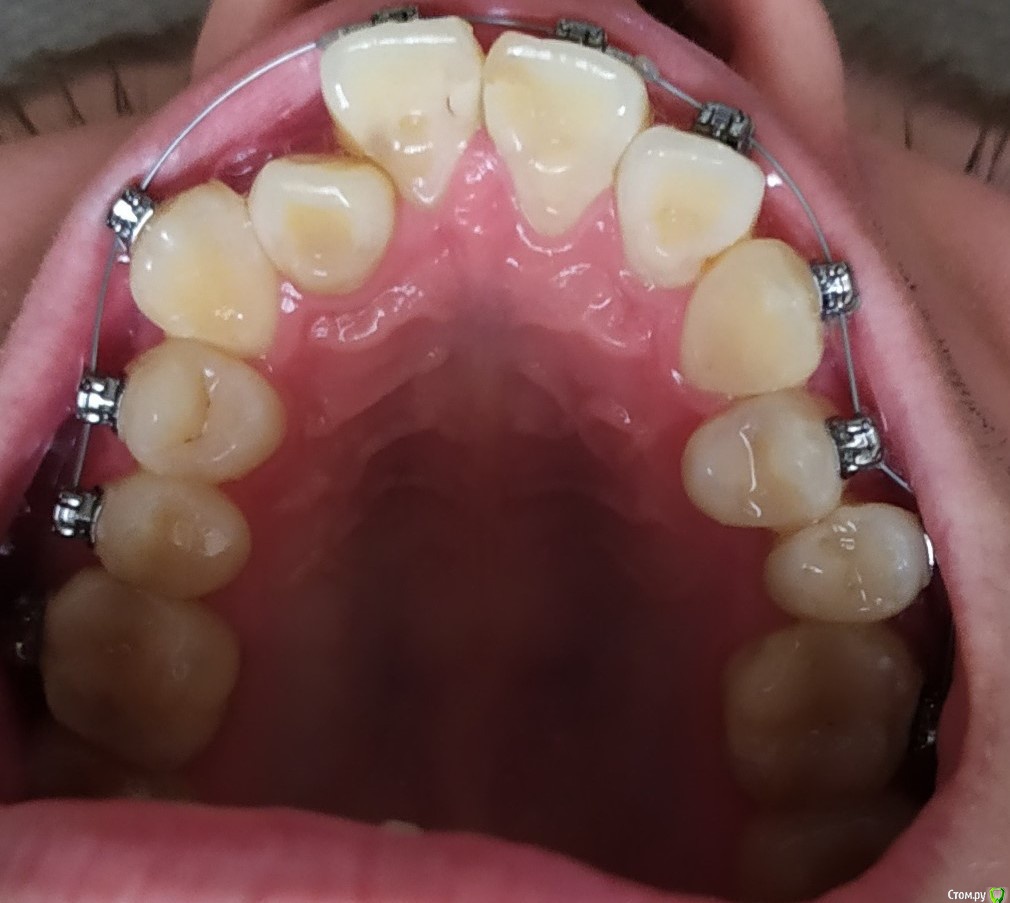

myshape Опубликовано 1 мая, 2020 Поделиться Опубликовано 1 мая, 2020 Здравствуйте! Историю моих зубов раскрывать не буду. Скажу только, что 2 месяца назад решился ставить брекет систему. После посещения рекомендованного мне ортодонта, направили на трг с диагностикой. Снимок прикрепляю.В итоге успел удалить 4 восьмерки и поставил сегодня БС Дэймон QИ тут меня накрыли сомнения и тревожные мысли после того как начитался про мой дистальный прикус. Вычитал, что это может быть скелетная проблема, а не только зубная. И надо применять хирургическое вмешательство. Теперь думаю, что удаление восьмерок было недостаточно и начал сомневаться в компетентности врача.Конкретно смущает то, что передние верхние резцы так сильно поданы вперед примерно на 45 градусов . И БС может усилить этот наклон.Очень хочется верить, что это мои домыслы и я стал себя накручивать. И врач знает, что делает. Но хотелось бы услышать мнение со стороны. Ссылка на комментарий

krokomot Опубликовано 3 мая, 2020 Поделиться Опубликовано 3 мая, 2020 подскажите пожалуйста, какой примерно должна быть схема лечения протрузии верхних резцов? достаточно ли будет только использование БС DamonQнужны расчеты на моделях и по трг, обычно начинают с расширенияи придание правильной формы верхней дуги, но это уже на усмотрение ортодонта, бреккет система это основной инструмент, могут использоваться и другие приспособления, на усмотрения доктора и в соотвествии с методикой лечения. 1 Ссылка на комментарий